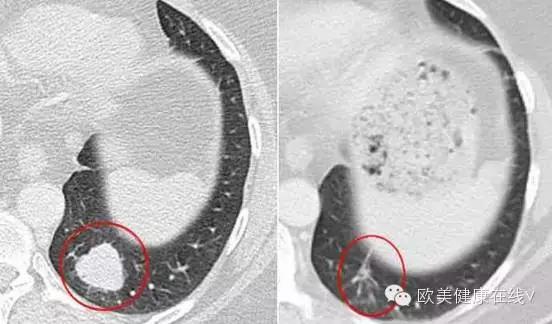

(图左、右红圈内为治疗前后病灶大小对比)

“原本被癌判了死刑的我,如今已多活了三年我的命运完完全全改变了!”